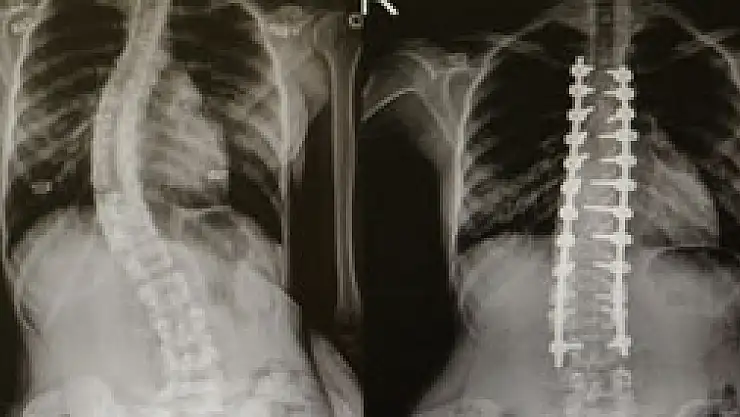

Skolyoz(omurga eğriliği) olan hastalar Ondokuz Mayıs Üniversitesi(OMÜ) Tıp Fakültesi'nde şifa buluyor.

Skolyozun genellikle çocuklarda görülen bir hastalık olduğunu ifade eden OMÜ Tıp Fakültesi Ortopedi ve Travmatoloji Anabilim Dalı Öğretim Üyesi Yrd. Doç. Dr. Mesut Kılıç, omurga eğriliği olan hastaların OMÜ Tıp Fakültesi'nde rahatlıkla tedavi edildiğini söyledi. Skolyoz cerrahisinde modern tekniklerin kullanıldığını belirten Kılıç, nöromonitörizasyon uygulamasıyla felç riskini yüzde sıfıra kadar indirdiklerini söyledi.

Skolyozun özellikle kız çocuklarda daha sık görülen bir durum olduğunu söyleyen Yrd. Doç. Dr. Mesut Kılıç, "Skolyoz hastalığı özellikle çocuklarda ve gençlerde gerek kozmetik gerekse fonksiyonel açıdan şikayetlere sebep oluyor. Tedavide çoğunlukla cerrahi dışı yöntemler uygulanır. Korse, egzersiz gibi. Fakat bazı hastalarda cerrahi tedavi gerektirmektedir. Cerrahide günümüzde modern teknikler kullanılmaktadır. Halk arasında platin diye bilinen uygulamalarla düzeltme sağlanmaktadır. Ayrıca son dönemlerde teknolojik gelişmelerle ortaya çıkan nöromonitörizasyon dediğimiz bir sistem uygulanıyor. Hasta uyutularak bilgisayara bağlanıyor. Ameliyat sırasında bir felç durumu var mı yok mu? Sinir yapılarında bir zedelenme var mı yok mu bunu bize bildiriyor. Halk arasında bu tür ameliyatlarda 'felç olursunuz' korkusunu biz çok duyuyoruz. Fakat bu uygulama ile felç riskini yüzde sıfıra yakın indiriyoruz" dedi.

Skolyoz ameliyatı olan Sedef Yavuz(17), "Omurgam yavaş yavaş sağ tarafa doğru dönmeye başlamıştı. Ağrılarım oluyordu. Artık dayanamıyordum. Oturduğumda ve yürüdüğümde bunalmaya başlamıştım. Tedavimin nerede yapılabileceğini araştırdım ve OMÜ'de bu tedavinin yapıldığını öğrendim. Doktorumla konuştuk ve ameliyat olmaya karar verdim. Ameliyata gülerek girdim. Ameliyattan sonra biraz ağrılarım oldu ama şimdi çok iyiyim" diye konuştu.